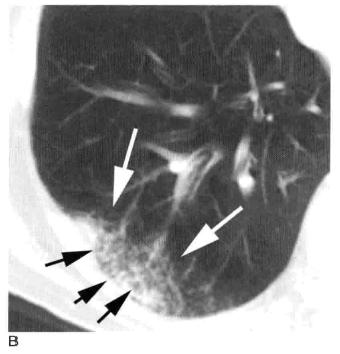

图4 实变,斑片状致密影

A.B. 支气管肺炎及小叶性实变患者增强HRCT显示单个小叶实变而周围邻近小叶正常,实变区小叶中心动脉(白箭头)和细支气管(黑箭头);C. 冠状面CT也显示斑片状实变影呈小叶性分布